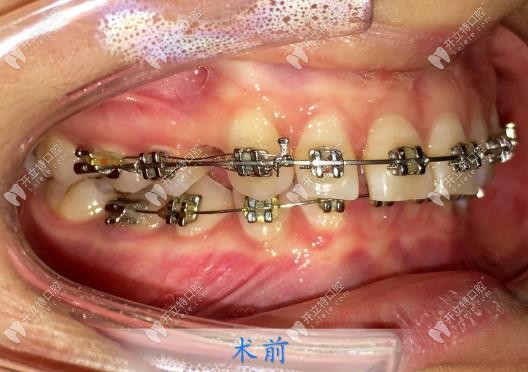

然后過了差不多半個月后,我就到院內(nèi)戴牙套了,楊醫(yī)生很細(xì)心,每一個托槽粘的都很認(rèn)真,他說這樣也是能防止后期托槽脫落帶來不必要的麻煩,我就更認(rèn)可楊醫(yī)生了!

矯正的周期是兩年,中間每個月都要復(fù)診,每次復(fù)診都是楊醫(yī)生為我加力的,直到取下牙套,結(jié)束矯正,我的牙齒都是楊永利醫(yī)生一手負(fù)責(zé)的!真的很認(rèn)真!